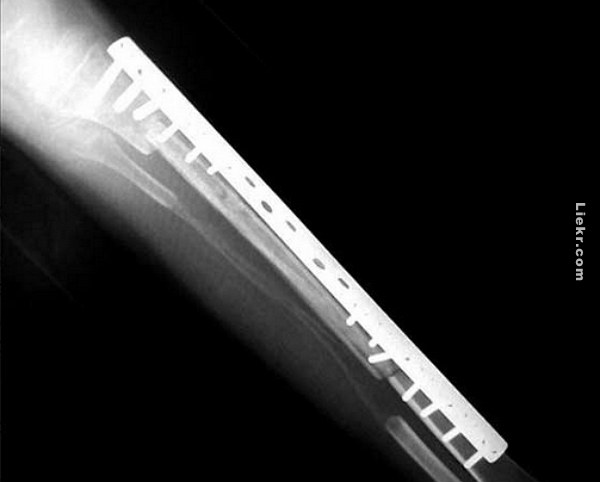

นายบรรดาศักดิ์ ไชยสาส์น ได้มีการด้ามเหล็กไทเทเนียมไว้ที่ขา เหตุการณ์การแข่งขันที่ไม่เป็นธรรมนี้เกิดขึ้นเมื่อประมาณกลางเดือนพฤษภาคม

จากผลการเอ็กซ์เรย์ทำให้เห็นได้อย่างชัดเจนว่าอะไรที่ทำให้เขาล้มลง…..

เรื่องนี้ถือว่าเป็นข่าวที่ดังมาในต่างประเทศ มีการติดตามกันอย่างต่อเนื่อง ซึ่งการฝังเหล็กไทเทเนียมเป็นการกระทำที่ผิดกฎร้ายแรงของการแข่งขัน ดังนั้นนายบรรดาศักดิ์ ไชยสาส์น จึงโดนระงับไม่ให้เข้าแข่งขันอีกต่อไป

นายบรรดาศักดิ์ ไชยสาส์นได้ให้สัมภาษณ์กับนักข่าวว่า ที่เขาต้องใส่เหล็กไทเทเนียมด้ามไว้ที่ขานั้น เนื่องจากระหว่างการแข่งขันกระดูกหน้าแข้งหัก จึงจำเป็นต้องด้ามกระดูกเอาไว้เพื่อให้แผลสมาน อย่างไรก็ตามทางคณะกรรมการและผู้จัดงานก็ไม่สามารถยอมรับได้….

จากการสอบสวนพบว่า ปกติแล้วต้องใช้เวลาเป็นปีกว่ากระดูกจะสมานติดกัน (กรณีกระดูกหนัก) แต่เขาใช้เวลาฟื้นฟูร่างกายเพียงแค่สองเดือนก็สามารถกลับมาชกมวยในศึกนัดนี้กับนายนพดล ชลอได้